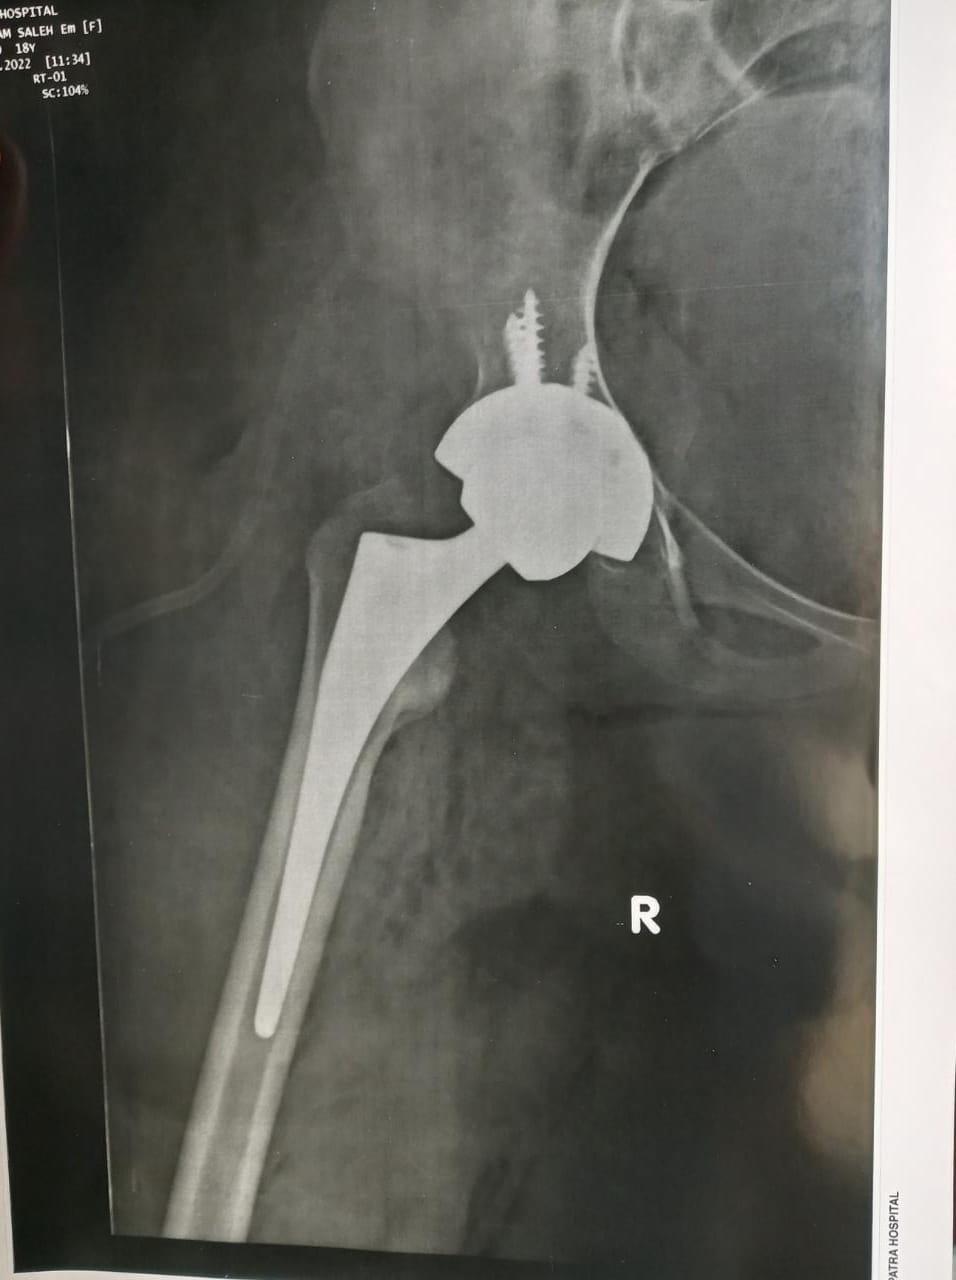

الاشعه بعد الجراحة تبين المفصل الصناعي الجديد مع تعويض تام للقصر.